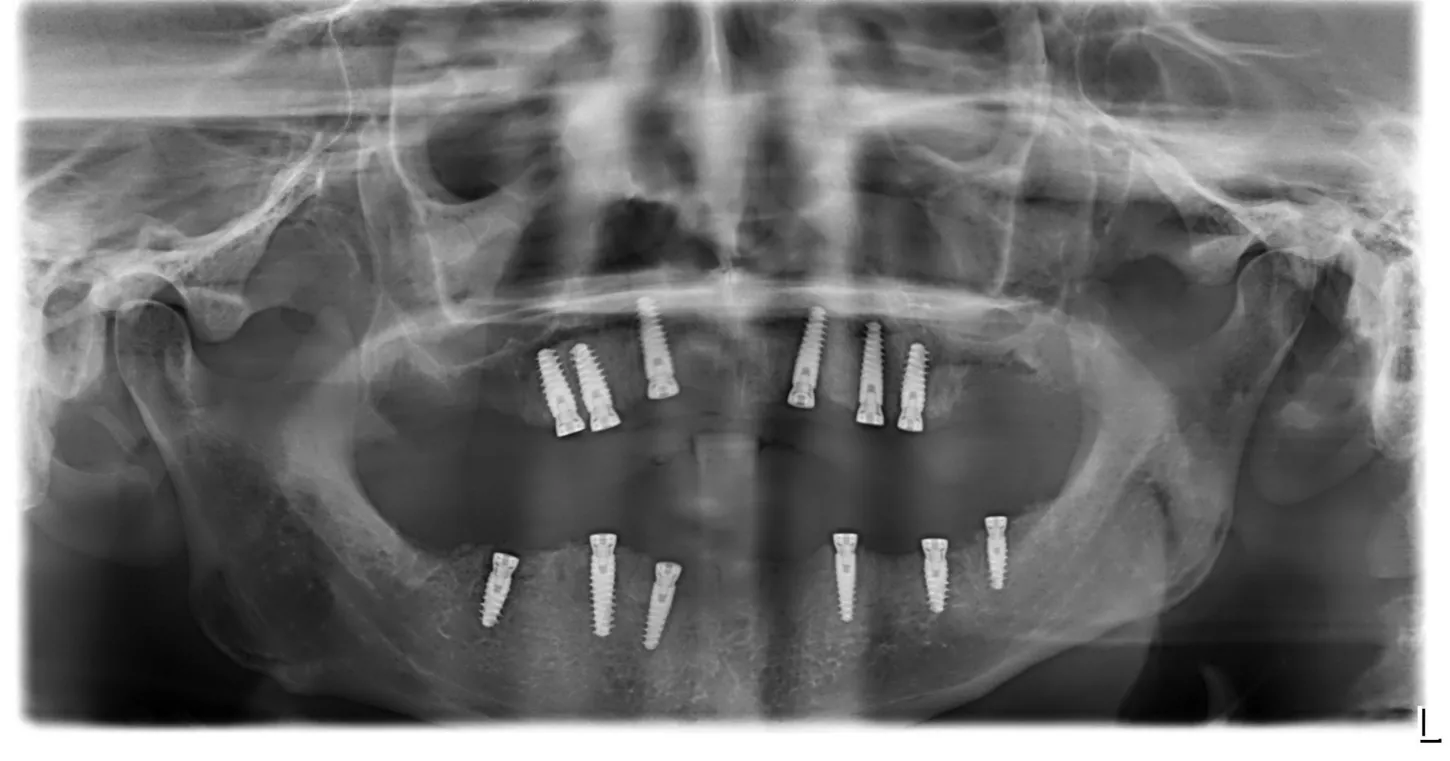

5a. 5b. The drilling sequence for Axiom X3® Tissue Level implants was according to the bone densities of specific quadrants in order to ensure optimal primary stability of the fixations. The implantation sites in the anterior and posterior zones were determined to be D1/D2 and D2/D3 respectively. The axis and dimensions of the implantation sites were confirmed using appropriate gauges.

A total of 6 Axiom X3 ® Tissue Level N platform implants were utilized on the upper jaw, comprising 3 units of Ø 4.0 x 10mm and 3 units of Ø 4.0 x 12mm, all with a gingival height of 2.5mm.

On the lower jaw, 6 implants were used, including 3 units of Ø 4.0 x 8mm, 2 units of Ø 3.4 x 10mm, and 1 unit of Ø 4.0 x 10mm, all with a gingival height of 2.5mm. The average torque measurement at implantation was recorded to be 60 N.cm.

22. Post operative radiographs of the implants and with restorations screwed in place.

22